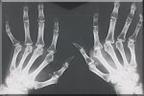

Reuma is de verzamelnaam voor meer dan tweehonderd reumatische aandoeningen. Dat zijn aandoeningen aan het bewegingsapparaat (botten, spieren, gewrichten, pezen) die niet het gevolg zijn van een ongeval of een blessure.

De meest bekende reumatische aandoeningen zijn: Artrose, Reumatoïde Artritis (RA), de ziekte van Bechterew, Artritis Psoriatica, Juveniele Chronische Artritis (jeugdreuma), weke-delen reuma. Daarnaast zijn er nog veel meer vormen van reuma.

Hoe herkent u reuma?

Een reumatische aandoening verloopt vaak grillig en vertoont uiteenlopende klachten. Algemene klachten van reuma zijn: stijfheid, pijn in de gewrichten, problemen met bewegen. Dat soort klachten kunnen natuurlijk ook het gevolg zijn van iets anders. Of u een chronische reumatische aandoening hebt weet u pas zeker als de huisarts of reumatoloog de diagnose heeft gesteld.